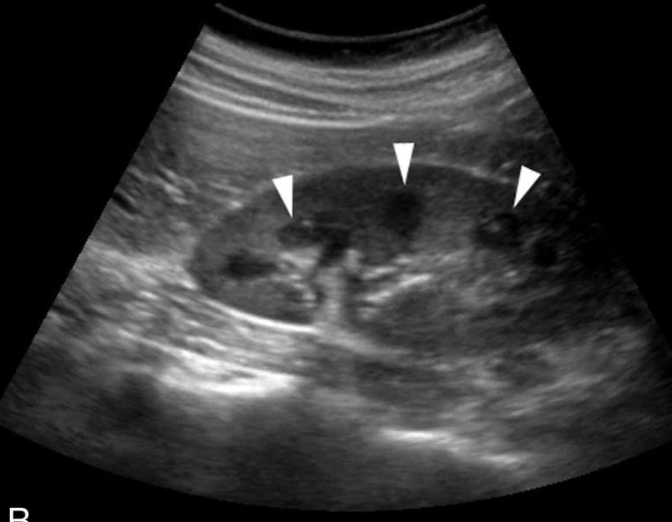

The right kidney is in contact with the:

liver, colon, and adrenal gland